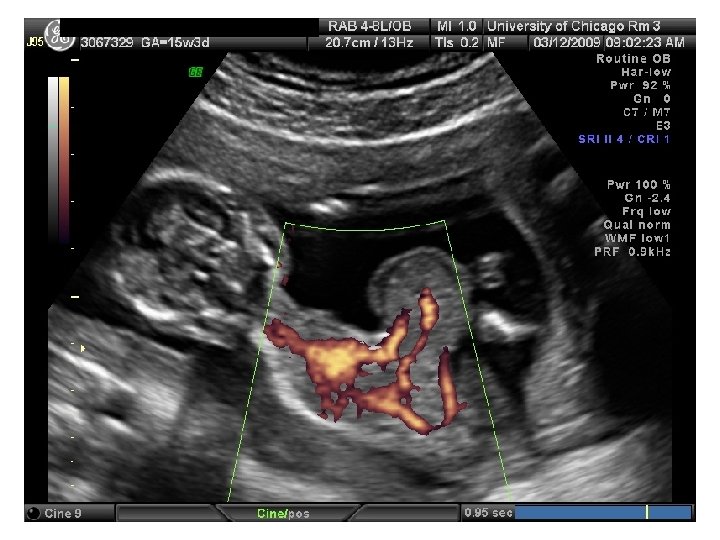

Twin Transfusion Syndrome

Requirements for diagnosis of TTTS 1. 2. 3. 4. the presence of a single placenta same-gender fetuses significant weight discordance significant amniotic fluid discordance often with a "stuck twin. "

Quintero Staging (TTTS) • Stage-based treatment of TTTS (Quintero, et al. AJOG May 2003) • I Donor’s bladder visible; dopplers normal II Donor’s bladder not visible x 1 hr; dopplers normal (ish) III Doppler’s critically abnormal in either (i. e. AEDF, RFDV, PUVF) IV Ascites, pericardial/pleural effusion, scalp edema, or overt hydrops V One/both twins dead

Management of TTTS • Amnioreduction • Septostomy • Photocoagulation